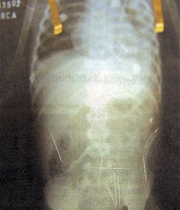

Médicos extrajeron 14 agujas al niño brasileño víctima de magia negra

Un equipo médico retiró otras 14 agujas del cuerpo a un niño brasileño de dos años de edad, al que su padrastro confesó haber sometido a un ritual de magia negra.

Las agujas retiradas estaban alojadas en la vejiga y en los intestinos y se suman a las otras cuatro que los médicos ya extrajeron de los pulmones y el corazón, que eran las que más preocupaban por su amenaza a la vida del menor.

En total le fueron clavadas 31 agujas, por lo que todavía hay 13 en el cuerpo del niño, 11 de las cuales no ofrecen riesgo vital y no serán retiradas, según los responsables del equipo médico.

Las otras dos, clavadas en la columna vertebral, serán sacadas la semana que viene porque todavía pueden representar riesgo para la salud del infante, que permanece internado en un hospital de Salvador, capital del estado de Bahía.